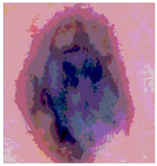

![]() | ![]() | ![]() | ![]() |

| Img1 | --- Pixel Intensity (0–255) ---> | ||

| Img2 | --- Pixel Intensity (0–255) ---> | ||

| Img3 | --- Pixel Intensity (0–255) ---> | ||

| Img4 | --- Pixel Intensity (0–255) ---> | ||

| Img5 | --- Pixel Intensity (0–255) ---> | ||

| Img6 | --- Pixel Intensity (0–255) ---> | ||

| Img7 | --- Pixel Intensity (0–255) ---> | ||

| Img8 | --- Pixel Intensity (0–255) ---> | ||

| Img9 | --- Pixel Intensity (0–255) ---> | ||

| Img10 | --- Pixel Intensity (0–255) ---> | ||